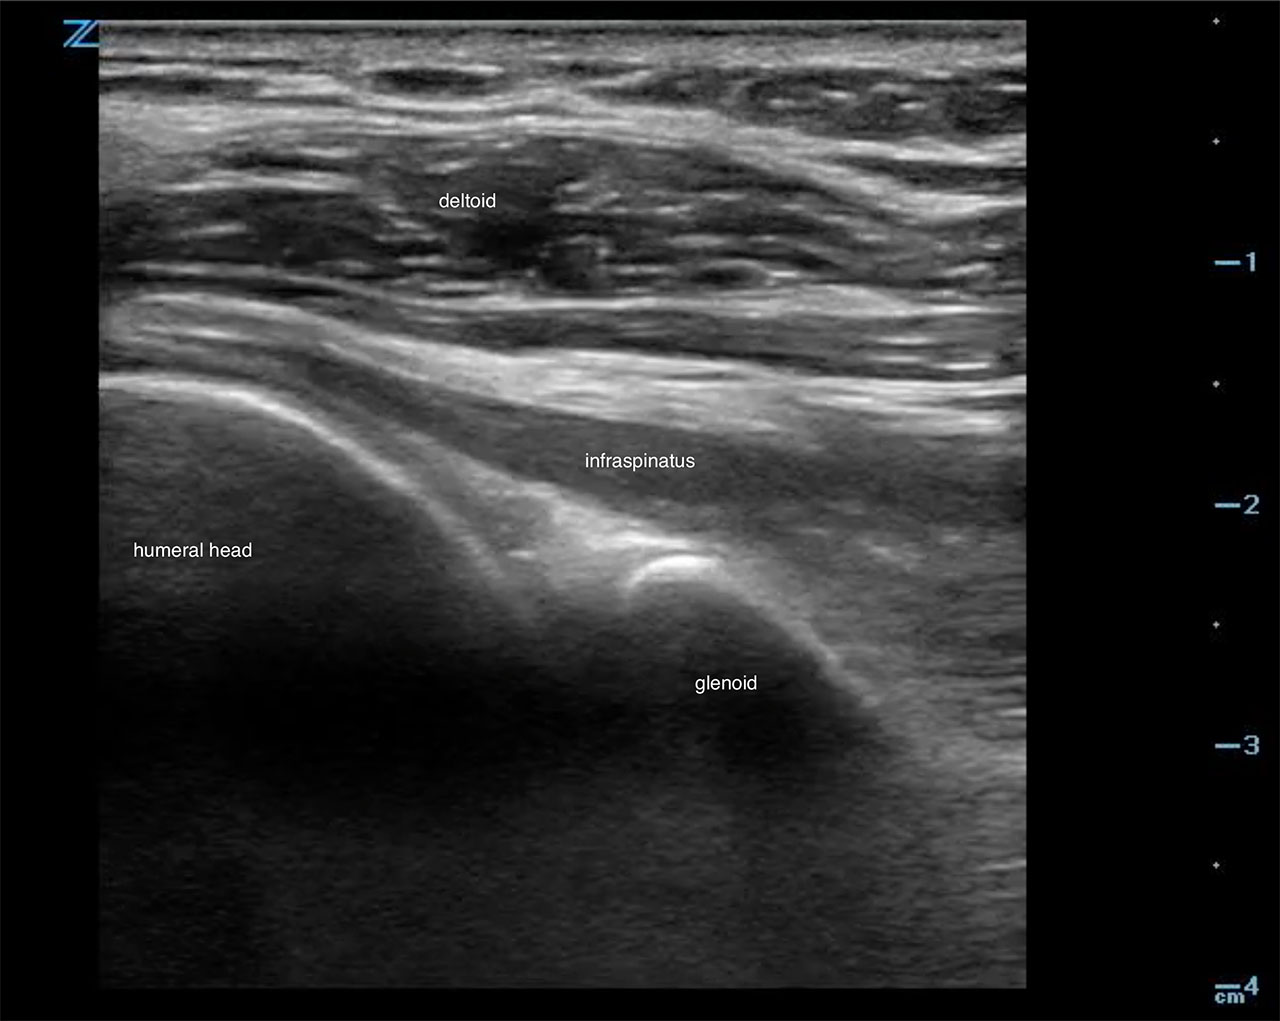

- The humeral head appears hyperechoic laterally.6

- It articulates with the glenoid fossa and contains infraspinatus tendon superficially.

- Scan laterally toward the humerus to obtain a view of the humeral head, glenoid fossa and superficially the infraspinatous tendon.6 (Fig. 9, Video 2)

- Figure 9. Ultrasound demonstrating normal shoulder

- An effusion is an anechoic collection just above the head of the humerus